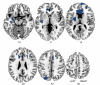

Results: Patients with trichotillomania showed increased grey matter densities in the left striatum, left amygdalo-hippocampal formation, and multiple (including cingulate, supplementary motor, and frontal) cortical regions bilaterally.